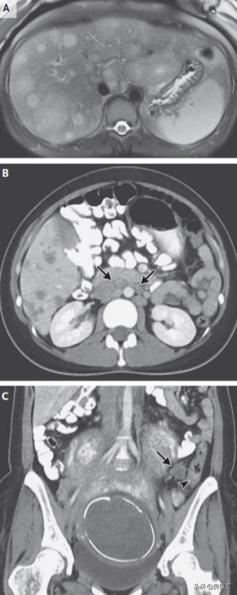

体温36.6°C,心率96次/分,血压105/68 mmHg,氧饱合度97%,右上腹压痛,妊娠子宫软,无肋骨痛。淀粉酶、脂酶和白细胞分类正常,多普勒超声可见胎心搏动,胎儿发育符合妊娠时间,生理指标正常。超声见肾脏和膀胱正常,肝脏弥漫异质性回声,有大量肿物。腹部MRI见肝脏多发病灶,T2加权像高信号,T1加权像低信号,最大损害7.4cm×3.9cm,部分中心坏死(图1A)。

给予别嘌醇和静脉补液,入院1天后转诊至第二家医院进一步评估。胸腹盆腔增强CT见大量低密度肝损害,部分边界清,最大损害8.2 cm,腹主动脉周围和门腔静脉周围淋巴结增大(图1B)。经皮肝活检提示转移性腺癌。患者未遵医嘱自行离院,经其产科医师转诊至麻省总院产科,此时孕33周。

图1 腹部影像学。A. 腹部MRI,T2加权像见多发高信号;B.盆腔CT见多发腹主动脉周围淋巴结(箭头);C. 盆腔CT见乙状结肠增厚(短箭头)伴邻近淋巴结肿大(箭头)。

患者疼痛剧烈,一直未能得到很好的解决。曾建议患者结束妊娠,然后进一步评估与治疗,但患者及其丈夫坚持要先明确原发肿瘤、治疗方案和缓解疼痛。胃肠组医师仔细研究了之前的腹部CT,发现乙状结肠增厚且邻近淋巴结增大,食管胃十二指肠镜和结肠镜见真菌样生长、部分阻塞肠腔肿物,直径5.0 cm,位于乙状结肠,行活检。